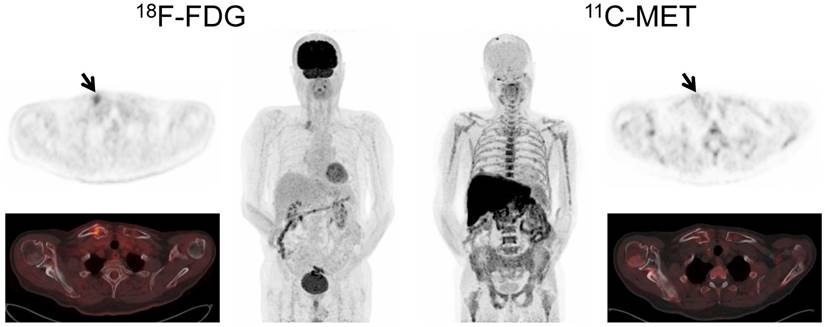

Imaging with MET identified more focal lesions than FDG in 44 patients (44/78, 56.4%, p<0.01), whereas FDG proved superior in only 2/78 (2.6%) cases (Figure 2). In the remaining 32/78 (41.0%) patients, an equal number of MM manifestations (identical lesions) was detected with both tracers.

Figure 2

Display of a patient (patient #57) with a history of Ig G λ MM. Imaging with both tracers was performed within 6 days. PET/CT with FDG depicted multiple hypermetabolic foci consistent with active MM which were partly missed by MET (transaxial slice of thoracic vertebra Th 7, arrows).

Interestingly, in 7/15 patients (46.7%) with EMD, MET detected lesions which were missed by FDG, whereas FDG outperformed MET in a single patient with hepatic EMD (Figure 3). In numbers, FDG detected a total of 44 EMD foci (soft tissue, n=20; lymph nodes, n=18; liver, n=4; lung, n=2), whereas MET depicted 72 lesions (p<0.01) in soft tissue (n=43), lymph nodes (n=24), and lungs (n=5). The lesions exclusively visualized by MET were found in soft tissue (n=23), lymph nodes (n=6), and lungs (n=3) (supplementary table 2).

Figure 3

Display of a patient (patient #60) with a history of Ig A λ MM. Imaging with both tracers depicted multiple hypermetabolic foci consistent with active MM. However, due to high physiologic uptake, extramedullary liver lesions were missed by MET-PET (arrows).